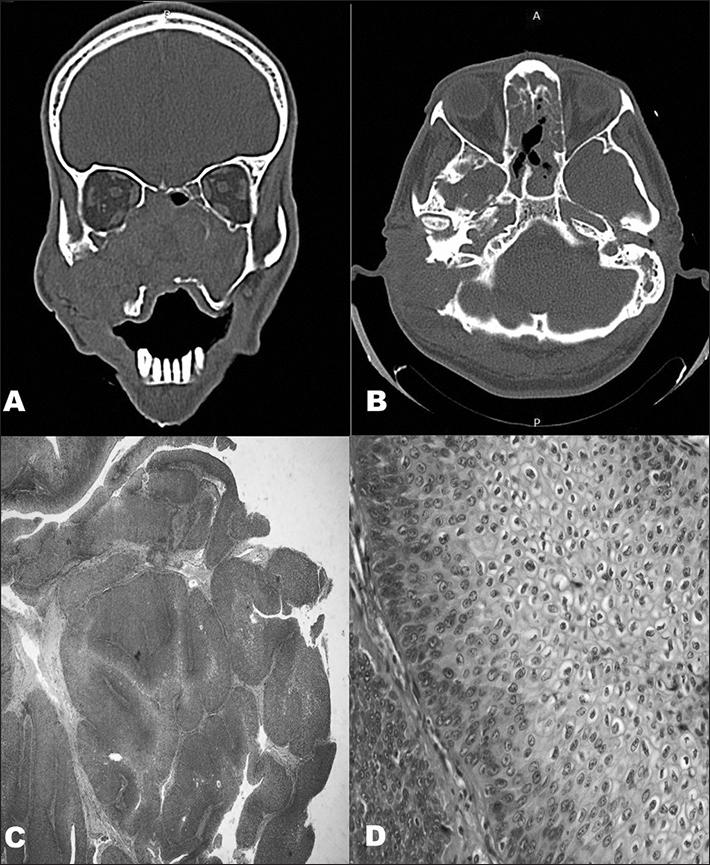

Sinonasal inverted papilloma involving the middle ear and the mastoid.

Braz J Otorhinolaryngol. 2012 Dec;78(6):122. doi: 10.5935/1808-8694.20120044.